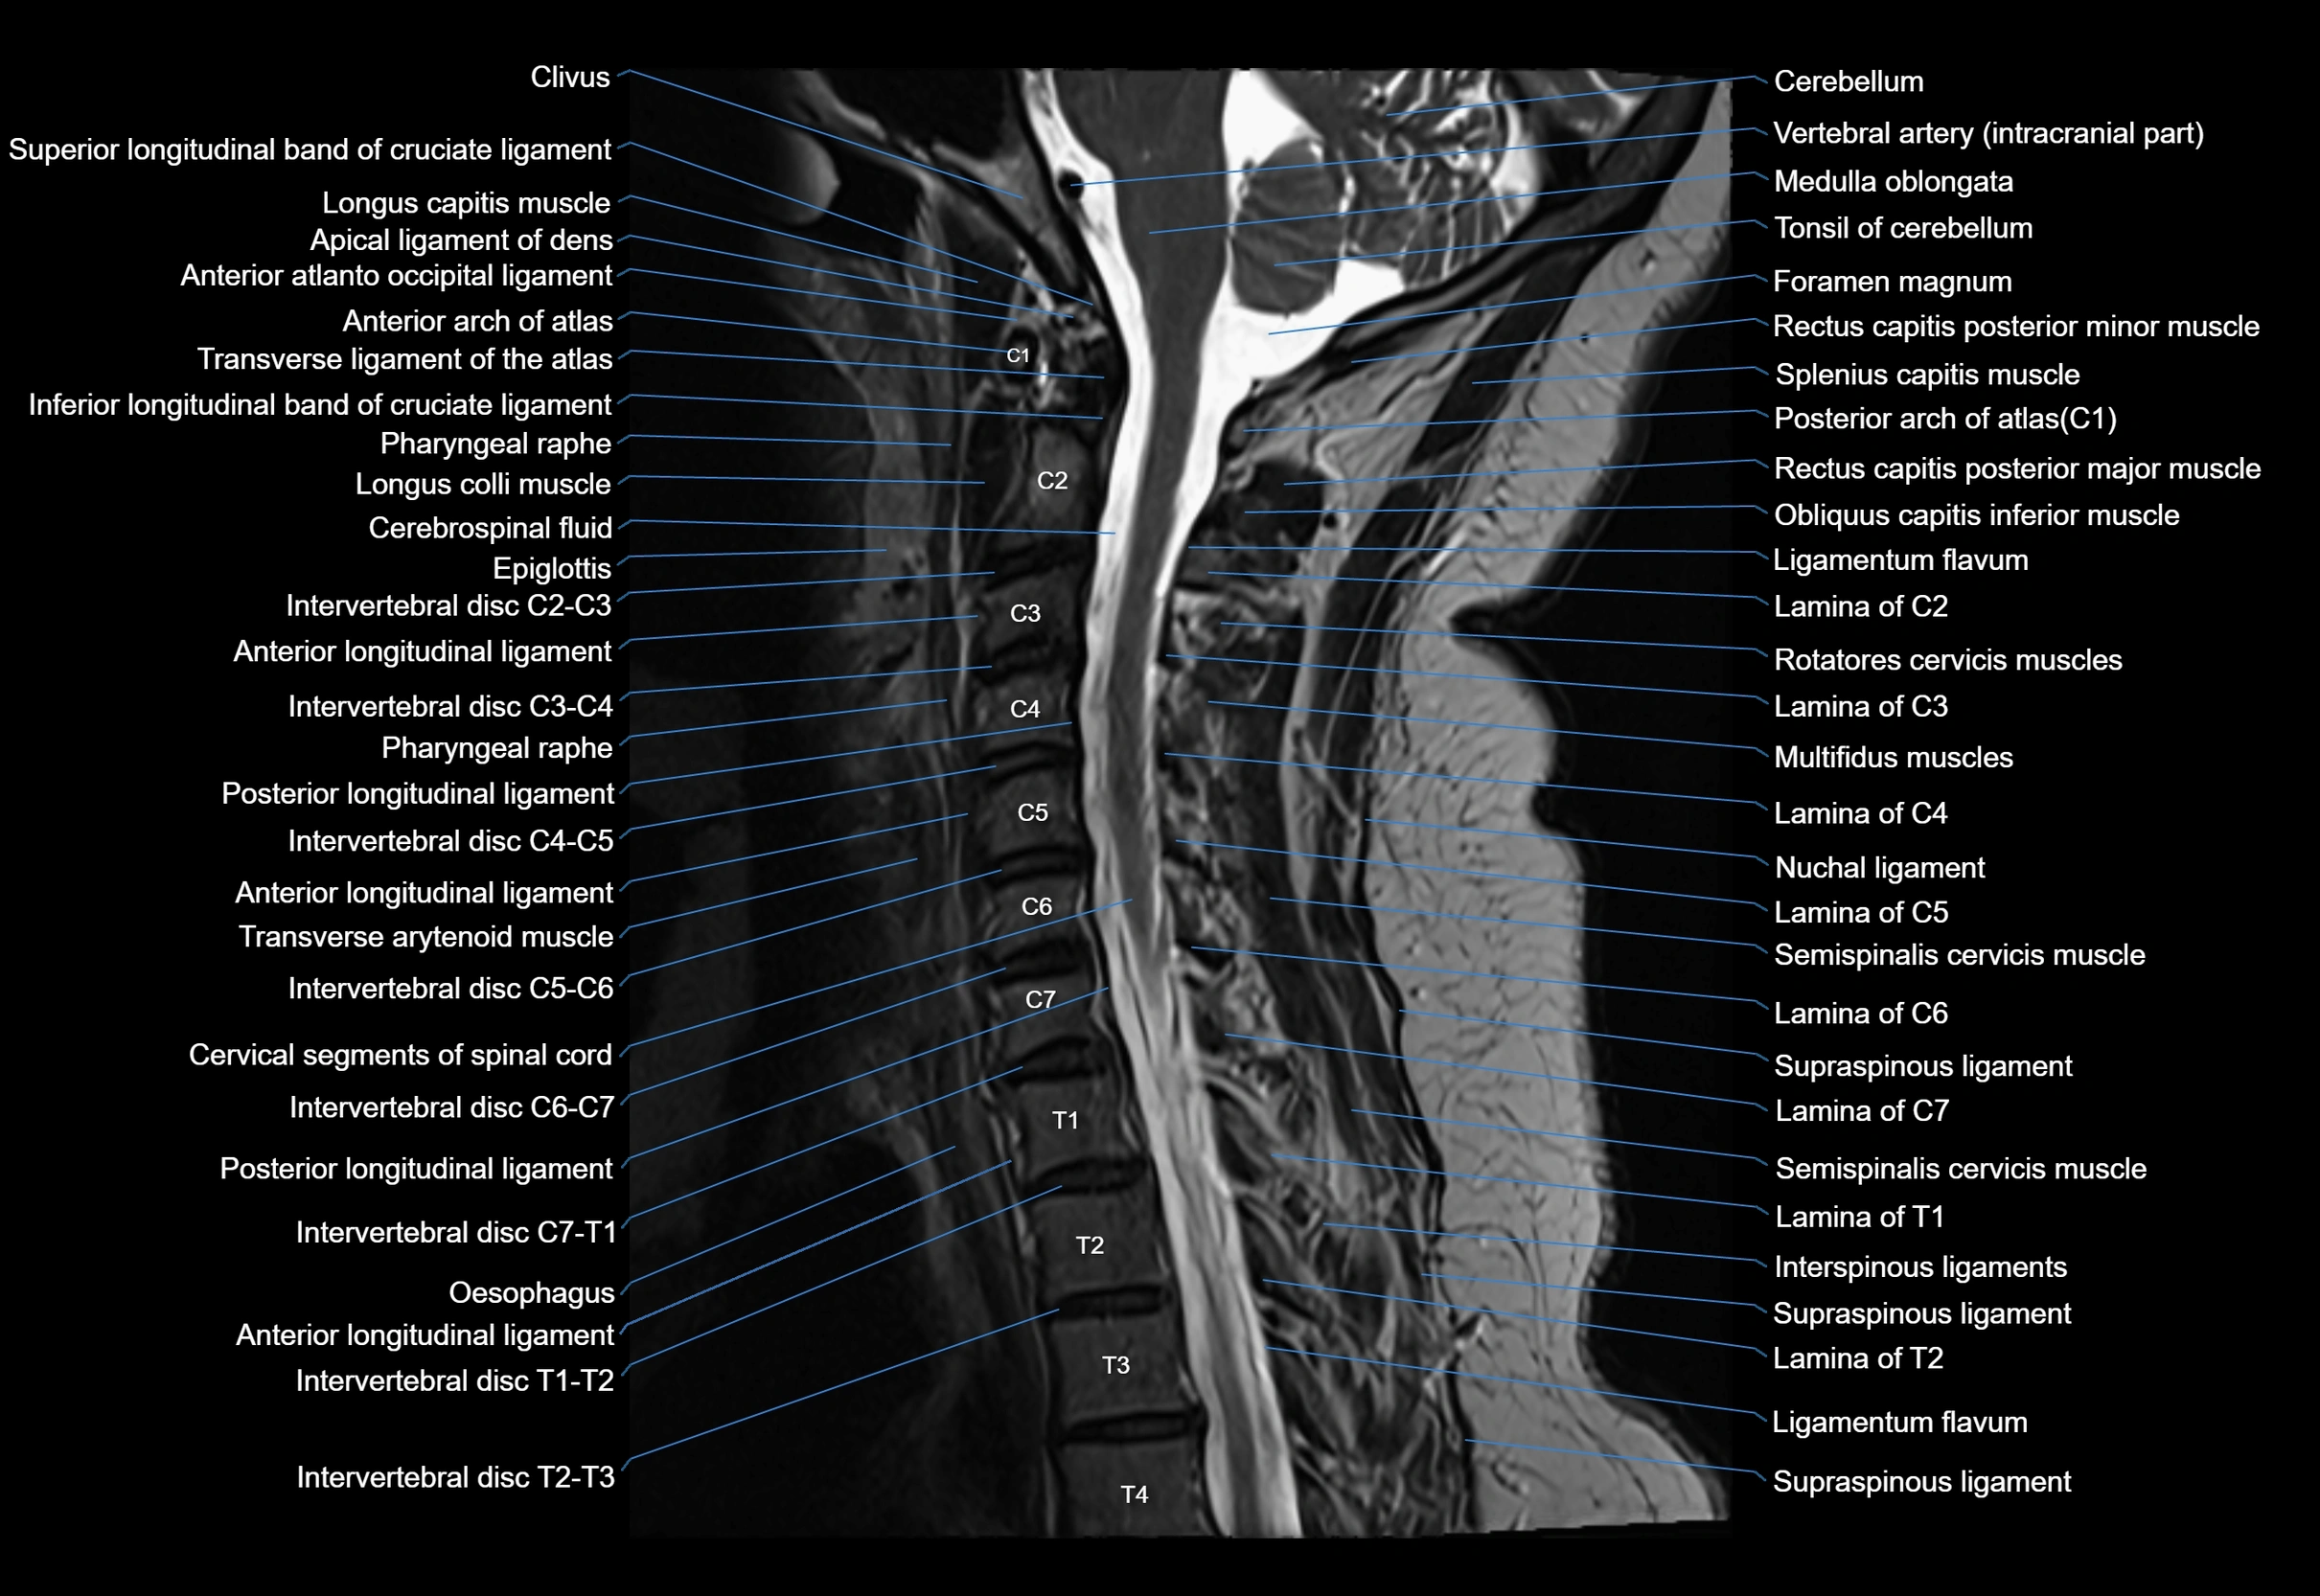

MRI image

image